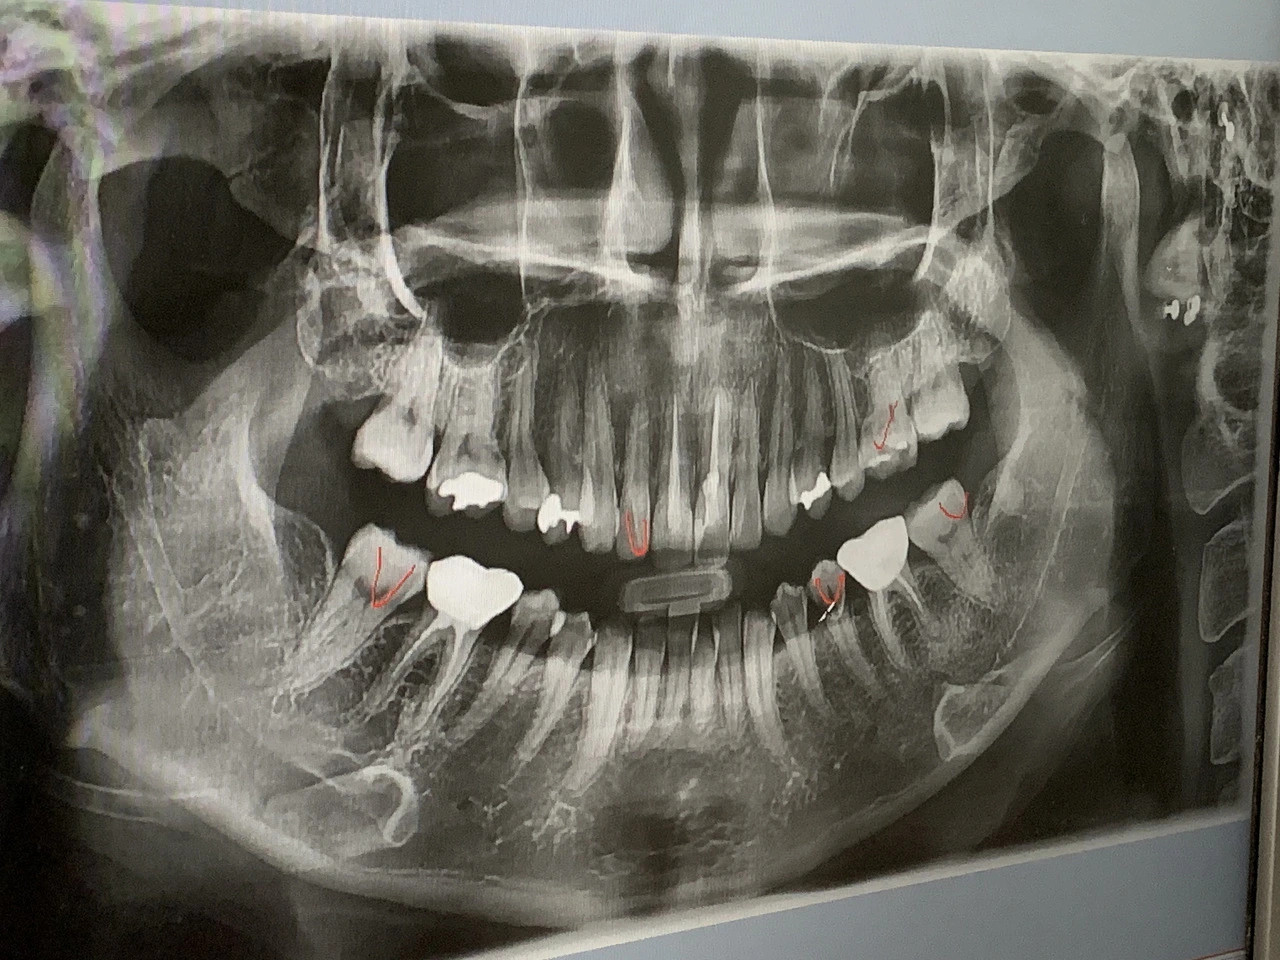

tempImageUwPxJX.heic 셀카보다 화려한 내 치아 사진..

옛 어르신들 말씀에 치아는 타고나는 오복 중 하나라 하였거늘, 그 오복을 나는 아슬하게 비껴갔나 보다. 내 치아로 말할 것 같으면... 일단 매우 잘 썩는다. 오죽하면 어렸을 때 초콜릿을 먹고 있으면 이빨이 썩는 게 느껴질 정도였다. 그럼에도 불구하고 초콜릿, 누가 크래커, 새콤달콤, 오징어 땅콩 등 치아에 안 좋은 군것질에 충실한 결과 내 치아는 멀쩡한 곳이 별로 없고 때워지거나 씌워진 몰골이다. 둘째로 잇몸이 약하다. 스케일링 한 번 하면 여기저기서 화산 터지듯 출혈이 생겨 침을 뱉을 때마다 피가 줄줄 나온다. 셋째로, 잘 깨진다. 최근에는 혀로 이를 훑다가 쎄한 느낌이 발끝부터 싹 퍼져오길래 치과로 달려갔더니 어금니가 다 깨져있단다. 분명 뭘 먹다가 그런 것 같은데 원래 몇 톤도 지탱한다는 게 사람 치아 아니었나요.. 마지막으로 변색이 잘된다. 커피는 안 마셔도 초콜릿과 홍차를 즐겼던 사람이라 그런가 치아가 비단 염색하듯 색을 아주 잘 머금었다. 미용의 이유로 미백을 하려 해도 앞선 여러 가지 이유로 치아가 더 상할까 봐 할 수 없었고 상당히 꾸질해진 치아로 살아가는 중이다. 삐쭉빼쭉한 아랫니는 덤. 이 역시 교정을 알아봤는데 치아 몇 개를 빼고 구조를 재배치해야 한다길래 있는 치아마저 약해질까 봐 포기.